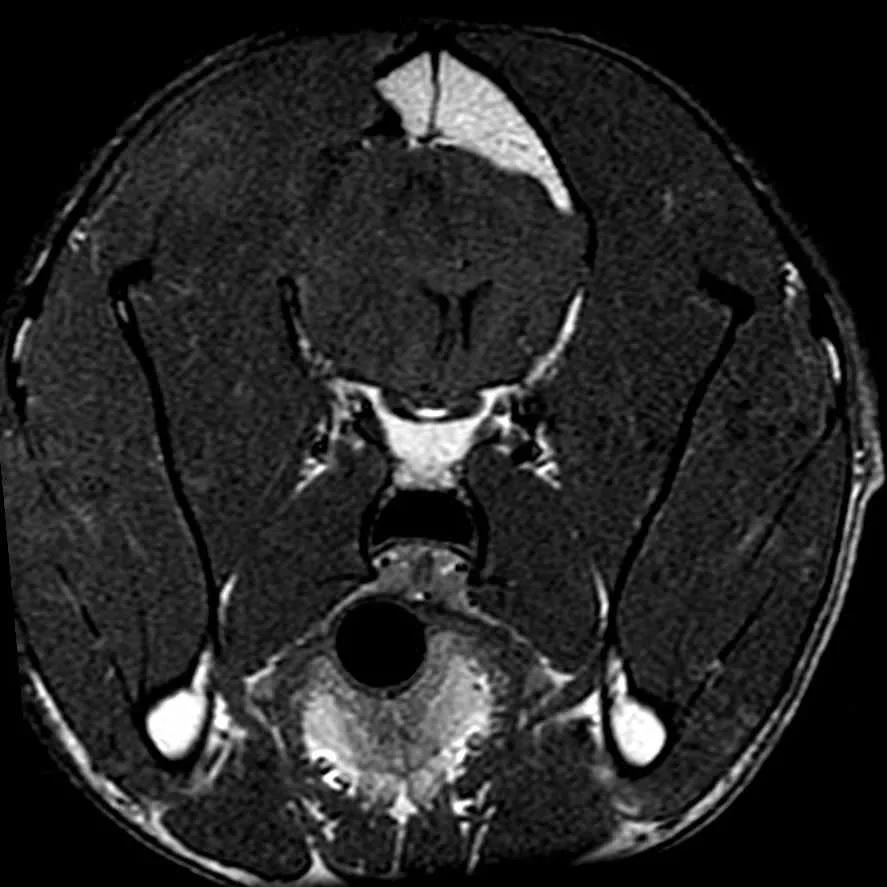

Post-Operative MRI In Dog With Brain Tumor

Surgery to remove a brain tumor is the most common reason we perform brain surgery in dogs and cats. As scary as a brain tumor may sound, the vast majority of pets do extremely well with surgery. Prognosis depends on the type of tumor, how fast it is growing, how much of the tumor can be removed, and what follow-up treatments are used.

We will only recommend surgery if we feel that the potential for a good outcome outweighs the risks. After performing an MRI, your veterinary neurologist will let you know whether brain surgery is a good option for your pet.